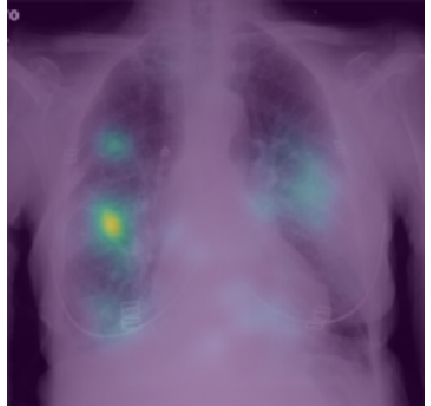

4.3 Domain experts’ evaluation of XAI methods

In most of the reviewed studies, the application of XAI comes down to the series of colorful images without any assessment about how valid these explanations are. Colored explanations obscure the original image, which makes it even more difficult to assess their correctness. In images with XAI heat maps, it is often hard or impossible to see pathologies and guess if the model works well. Raw lung images shall be put next to explanations. Also the explanations should be interpreted or validated by radiologists. Otherwise, they are redundant and contribute nothing to the trustworthiness of the model.

Together with the radiologists, we analyzed the explanations from the discussed works. In the following paragraphs, we discuss the most common mistakes or inappropriate explanations.

In the first example, in Figure 5a), the model focuses on clavicles, scapulas, and soft tissues, which are outside the lungs. Very likely, the model predicts illness based on an improper part of the image. Location of the areas marked by explanation should be inside the chest on the lung tissue because COVID/̄19 lesions are not located on, e.g., lymph nodes. Moreover, there are some elements that cannot be considered as decision factors like imaging artifacts (cables, breathing tubes, image compression) or embedded markup symbols [37]. To prevent the model from focusing on irrelevant features, in some studies, the lungs were segmented, and their background was removed [31, 32, 34, 45, 50]. However, it may not help when some imaging artifacts are present in the area of the lungs.

The second example, in Figure 5b) shows that the model does not take the lesions into account. The model states that parts of the lungs other than the ones marked by the radiologist are relevant for model prediction. Explanations that “roughly indicate the infection location” [32] are not acceptable for the robust model. The model should do this with the accuracy of the pixel marked by radiologists as relevant.

The third example, in Figure 5c), visualization is not clear. The study describes a different XAI method than the one present in the image. Moreover, this visualization highlights the whole image, and it is not possible to guess which features took part in the prediction. It is important to point out that some explanation methods can give clearer results for a specific type of DNN and for a specific domain.

The last example, in Figure 5d) is blurred. The image of the lungs is improperly taken, and the process should be repeated. The current image is useless for the accurate diagnosis process. Such images should be removed during data resource verification before model training.